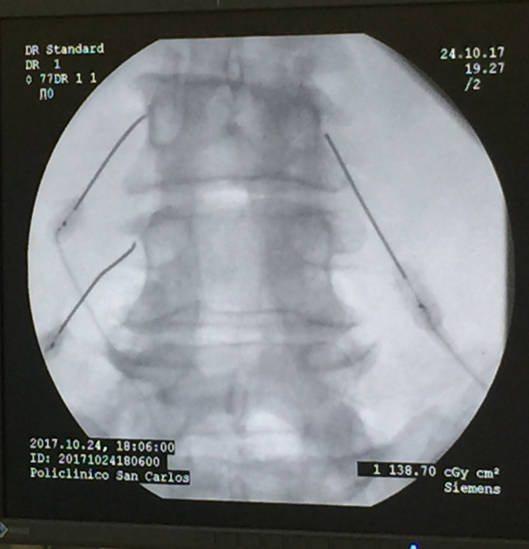

La rizolisis es una técnica que se hace en quirófano con anestesia local y sedación. Se realiza en quirófano porque es necesario utilizar un aparato de rayos.

Una vez en quirófano nos colocaran boca abajo, se localiza bajo control radiológico la zona por la que transcurren los nervios sobre los que vamos a realizar la radiofrecuencia

Utilizaremos un anestésico local para insensibilizar la piel e introduciremos un aguja y la situaremos en el recorrido del nervio a insensibilizar. Posteriormente realizamos una estimulación de la zona para detectar si tenemos la aguja correctamente posicionada y no es posible lesionar la médula o los nervios motores, recuerda que se trata de alterar únicamente los nervios sensitivos de la articulación facetaria. En caso de tener un estímulo no adecuado reposicionamos la aguja en la posición adecuada

Una vez que tenemos el catéter correctamente posicionado procederemos a realizar la rizolisis del nervio.